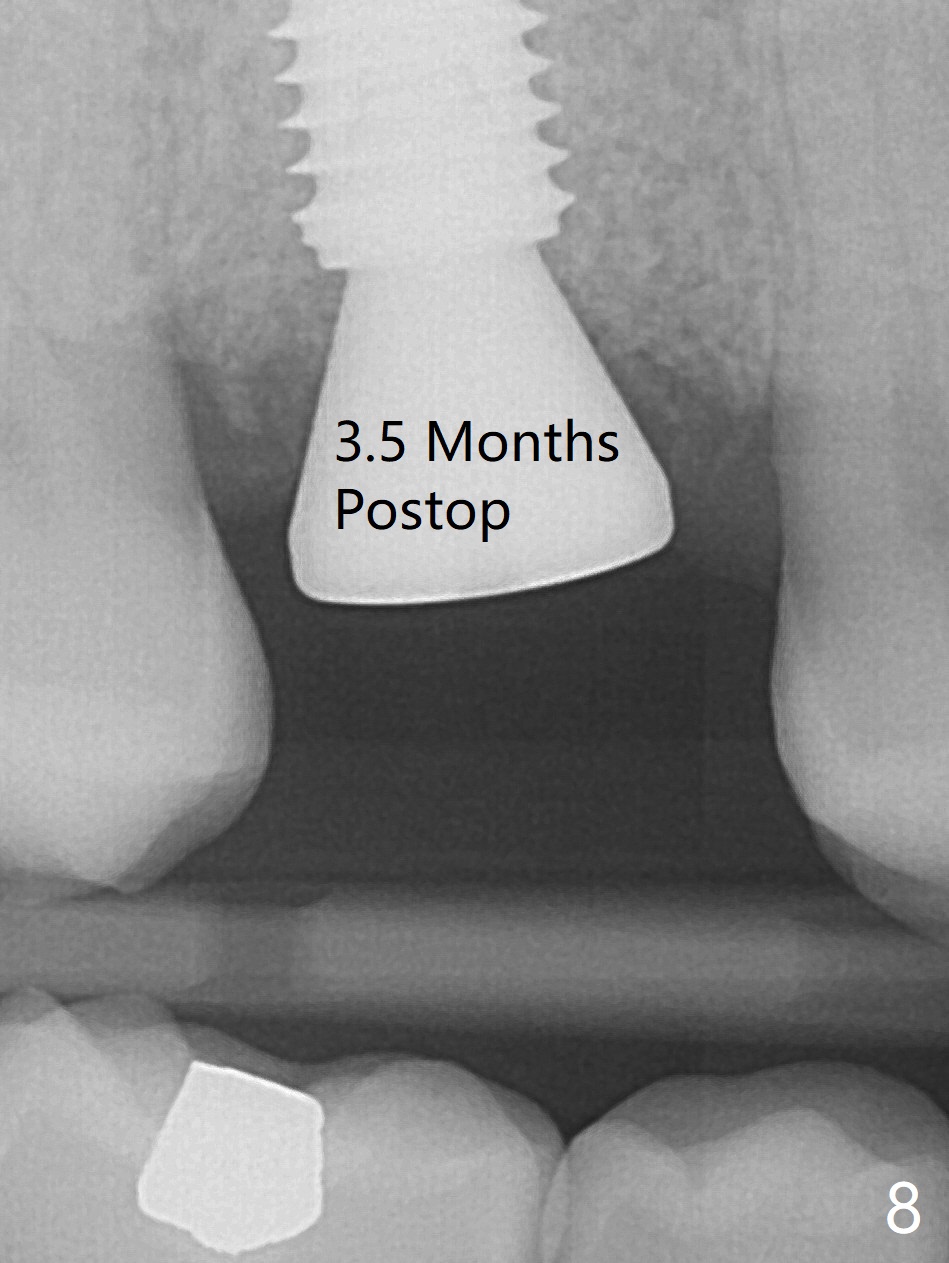

While the tooth #3 has a mesiodistal crack line, etiology may be due to chronic periodontitis with bruxism. After extraction, there is granulation tissue attached to the distobuccal (DB) root. The DB socket is larger than the mesiobuccal one (Fig.1). Osteotomy is initiated in the DB slope of the septum for 10 mm (Fig.2,3). Since there is ample apical bone, the depth of the osteotomy increases to 11.5 mm. When a 5x10 mm dummy implant is placed, primary stability is satisfactory (Fig.4 (yellow line: apical space)). The definitive implant remains the same dimension with deeper placement (Fig.5,6 (~ 20 Ncm)); with placement of a 6.5x4(3) mm abutment and Vanilla/Osteogen Graft (*), an immediate provisional is fabricated in place (without taking out for trimming) with sufficient clearance with the opposing dentition. It appears that the moderately long implant (10 mm) is able to achieve primary stability for immediate placement. When the provisional is removed 2 months postop, bone graft seems to be adhered to the socket (Fig.7). To improve local hygiene, the provisional does not return. The implant seems to have osteointegrated 3.5 months postop (Fig.8). The crown/abutment is loose approximately 1 year post cementation. Due to her daughter's contracting COVID 19, she postpones returning for approximately 1 year. The access hole is opened, crown/abutment (6.5x4(4) mm) removed, proximal contacts reduced, crown/abutment reseated without certainty. BW shows incomplete seating probably due to bony interference (Fig.9). A 5.5x4(4) mm can not be seated (bouncing, probably due to soft tissue interference). When a 4.5x5(4) mm abutment (UF) is seated, hand tightening is smooth, confirmed by BW (Fig.10). Two weeks later, the new crown is cemented intraorally. The crown/abutment is removed for cleaning. The abutment screw is torqued at 20 NCM.